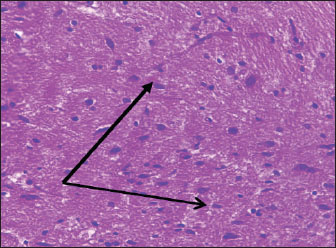

Brain of control group appeared normal structure of tissue with manifestation of Purkenji cells (Fig. 1), whereas sodium benzoate administration at low dose (200 mg/kg) occurred several histological lesions as hypertrophy of neurons (Fig. 2), pair nuclei arranged encompassed with clear space (Fig. 3), bleeding with degeneration of nerve cells (Figs. 4 and 5), respectively. In addition, lesions such as vacuolation, congestion, and accumulation of inflammatory cells were also evident (Figs. 6 and 7). However, severe histopathological lesions were observed following high-dose of sodium benzoate exposure, such as degeneration of neurons stained in dark blue (Fig. 8), prominent vascular duct with inflammation (Fig. 9), vacuolation, edema, and clear congestion as seen in Figures 1012, respectively.

Fig. 1. Points to the brain of control group: normal structure and manifestation of purkinje cells (H&E) (100 ×).